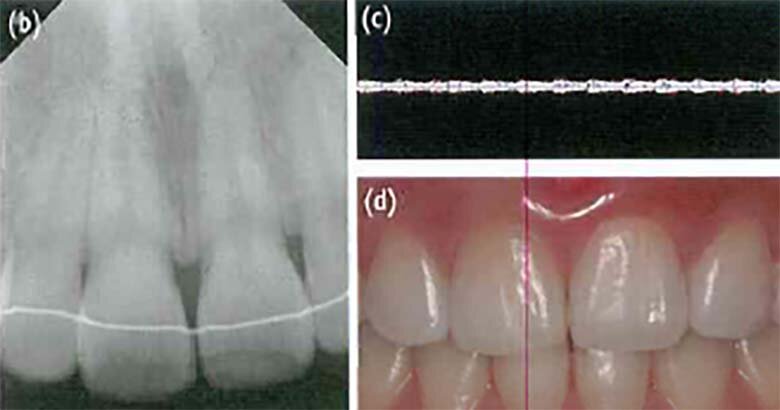

30-летняя пациентка обратилась в нашу клинику для дальнейшего лечения травмированных передних зубов. Она получила травму при падении 2 недели назад и посетила местную клинику сразу после травмы. Смещенный зуб № 21 был шинирован с помощью композитной смолы и проволоки от зуба № 13 до зуба № 23, а затем местный дантист направил ее в нашу клинику. На периапическом рентгенографическом изображении корневая и периапикальная области были нормальными (рис. 2а). Зуб №21 показал отрицательные реакции при температурном тесте и ЭОД, положительную реакцию на перкуссию, и розоватое изменение цвета (рисунок 2б). Другие зубы показали нормальные реакции во всех тестах. В ультразвуковом допплеровском исследовании зуб №21 показал нормальную пульсирующую реакцию как у других зубов, кроме того мы услышали ритм пульсации из динамика (рисунок 2в). Через 4 недели после травмы зуб № 21 снова показал нормальную реакцию на перкуссию. В других тестах результаты были такими же, как и при предыдущем визите. Через 6 недель после травмы зуб № 21 по-прежнему демонстрировал розоватое изменение цвета и отрицательные реакции на температурный тест и ЭОД. Через 10 недель после травмы оттенок зуба № 21 вернулся к норме (рисунок 2г). Через 12, 16, 20 и 24 недели после травмы пациентка вообще не испытывала никакого дискомфорта. В ультразвуковом допплеровском исследовании зуб № 21 показал жизнеспособную реакцию, но он не реагировал на холодовой тест или ЭОД. На периапикальном изображении корневая и периапикальная области находились в нормальном диапазоне. Отрицательная реакция сохранялась на протяжении всего периода наблюдения в течение 9 месяцев. На тот момент пациентка была беременна и хотела отложить свой следующий визит до родов.

Рисунок 2. (а) В случае 2 зуб № 21 был шинирован в местной клинике после подвывиха, произошедшего за две недели до того, как пациентка обратилась в нашу клинику. Зуб показал отрицательную реакцию на температурный тест и ЭОД и положительную реакцию на перкуссию (b) Зуб № 21 показал розоватое изменение цвета; (c) В ходе ультразвукового допплеровского исследования зуб №21 показал нормальную пульсирующую реакцию, как у других зубов; (d) Через 10 недель после травмы оттенок зуба № 21 пришел в норму.

Рисунок 3. (а) В случае 3 наблюдалось желтовато-коричневое изменение цвета зуба № 11; (b) Пространство коронковой пульпы было облитерировано, тогда как пульповое пространство присутствовало в области корня. Не наблюдалось радиолюминесценции в периапикальной области, но вершина корня была слегка укорочена; (c) В ультразвуковом допплеровском исследовании зуб №11 показал изображение, типичное для здорового зуба; (d) Пациентка была удовлетворена оттенком зуба №11 после витального отбеливания.